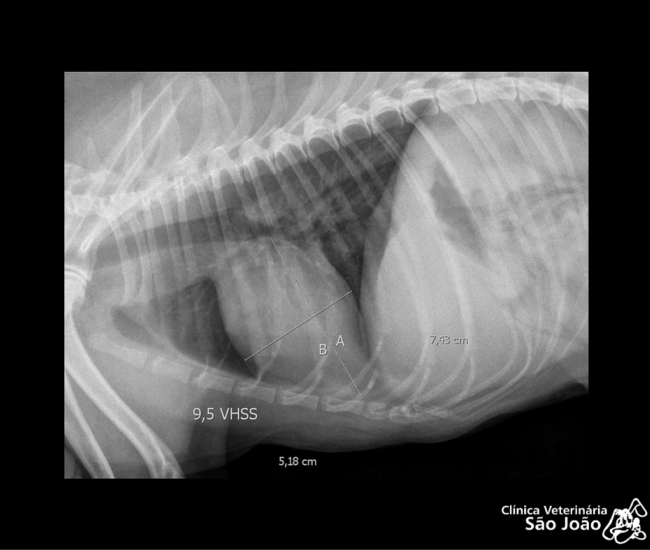

- Diferentemente do raio-x analógico, este raio-x oferece altíssima definição e todas as vantagens da tecnologia digital. É possível aproximar a imagem, trabalhar o contraste, exposição.O software permite ainda avaliações da medida cardíaca do animal e graus de displasia coxofemoral, por exemplo – explica o Dr. Nardeli Lucena.

- sofware com medidas para avaliações do tamanho cardíaco e medições dos ângulos de Norberg para diagnóstico e classificação de displasias coxofemorais;